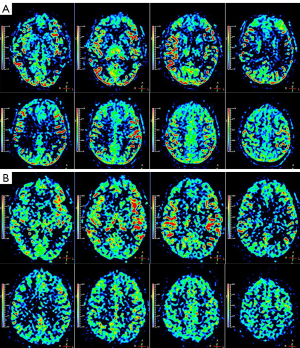

The patient’s MDT initially considered intervention or revascularization surgery as the optimal treatment to reduce the frequency of recurrent TIAs and the risk of infarction. However, repeated ASL indicated that the patient’s cerebral hemodynamic impairments and collateral blood flow were not consistent with those of typical MMD. The patient’s ASL data were acquired with three-dimensional pseudo-continuous ASL (3D-pCASL) using the following parameters: labeling duration =1.5 s, postlabeling delay (PLD) =1.5/2.5 s, repetition time (TR) =3.7/4.7 s, echo time (TE) =11 ms, field of view (FOV) =240 mm × 240 mm × 85 mm, matrix =64×64, thickness =6 mm, and duration time =5 minutes and 21 seconds/6 minutes and 47 seconds. In 2013, the patient’s 3D-pCASL images showed serpiginous high signal intensity in the bilateral cerebral cortex and sulcus at a PLD of 1.5 s (Figure 4A), and, less prominently, in the bilateral temporal and parietal cortex at a PLD of 2.5 s (Figure 4B). From 2013 to 2020, 3D-pCASL at PLD of 1.5 and 2.5 s continuously demonstrated bright hyperintensity in the cerebral symmetric cortical surface. In 2021, the 3D-pCASL-based dynamic MRA referred to as “four-dimensional magnetic resonance angiography (4D-MRA)” and 3D-pCASL were performed on a new 3.0-Tesla MRI scanner (Ingenia CX, Philips) using 32-channel head coils. The latest ASL images showed hyperintense signal bands in the bilateral hemisphere at a PLD of 1.5 s (Figure 5A) and, much more prominently, at a PLD of 2.5 s (Figure 5B). Meanwhile, 4D-MRA data were acquired with the time-resolved angiography non-contrast-enhanced (TRANCE) technique using the following parameters: TR =9.3 s, TE =4.8 s, FOV =210 mm × 210 mm × 80 mm, spatial resolution =1.2 mm × 1.2 mm × 1.3 mm, matrix =172×130, thickness =1.3 mm, label delay =200 ms, label gap =20 mm, phase interval =200 ms, phases =10, and duration time =2,200 ms. Symmetrical emergence of bilateral PCAs was observed, and intracranial collaterals originating from the bilateral PCAs were clearly shown on the dynamic 4D-MRA (Figure 5C).

Between 2013 and 2020, the intensity of ATA on the patient’s ASL images at a PLD of 1.5 s was much more significant than that of 2.5 s, which suggested that the antegrade blood flow was comparatively faster. The latest ASL in 2021 showed that the intensity of ATA at a PLD of 2.5 s was much more intensive than before, which may suggest that the arterial transit time of the collaterals is longer than the anterograde blood flow. ATA is dependent on the arterial transit time and is influenced particularly by the labeling time and PLD. The decreased and slow blood flow might induce an ATA; therefore, cortical flow in moyamoya patients may resemble this hemodynamic status. The strength of the ATA alters according to the PLD value because the delayed blood flow due to stenosis or occlusion still remains in the cortical surface (24,27). Regarding this patient, ASL acquisitions with both shorter and longer PLD dramatically demonstrated conspicuous ATA in the bilateral hemispheric cortex, and this status has lasted almost 10 years to date. ATA has been reported to correlate with the development of collateral circulation and to reflect the presence of leptomeningeal collaterals on DSA (28). The balance of hemodynamics and compensated perfusion of this patient relies on slow flow from the collaterals of the posterior circulation, which prolongs the mean transit times of arterial blood flow and creates ATA on 3D-pCASL images. 4D MRA is a 3D-pCASL-based dynamic MRA with long labeling duration, which can ensure visualization of the complete arterial trees from proximal to distal vessels with adequate image quality (29). The patient’s latest 4D-MRA clearly shows the presence of collaterals mainly from the bilateral PCAs. Consequently, preservation and improvement of collateral blood flow can provide protection against future strokes and reduce the frequency of ischemic symptoms while effecting a concurrent reduction in collaterals.